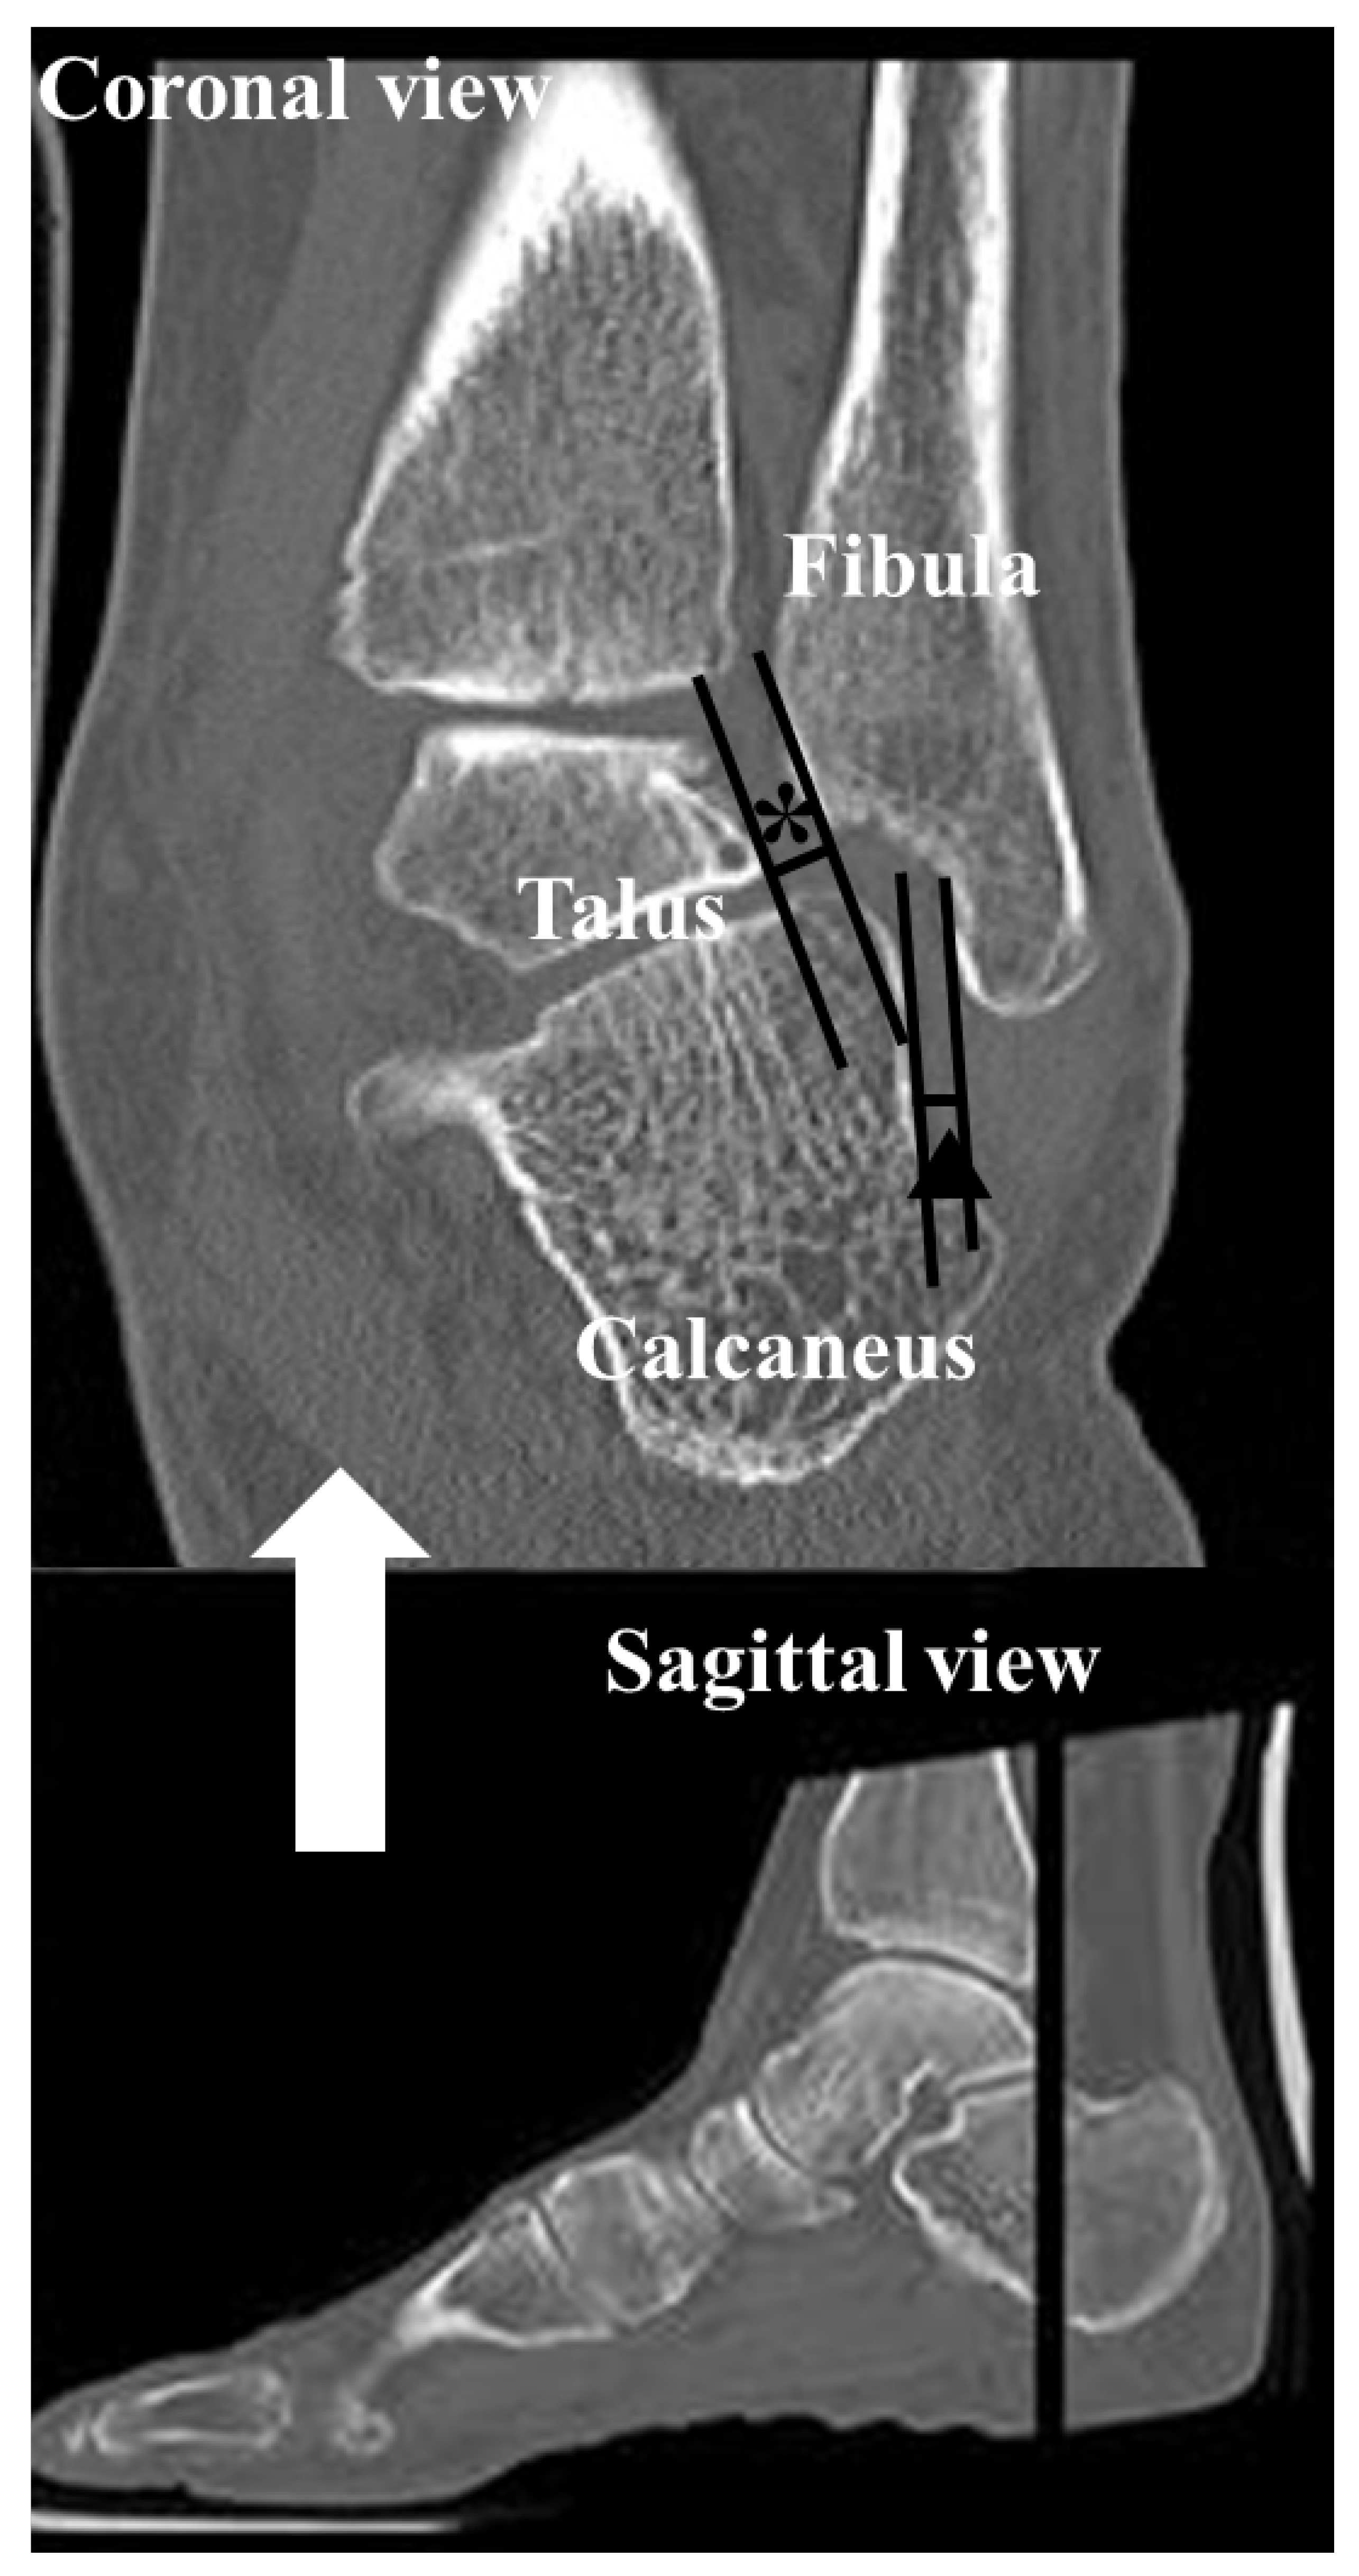

To assess the alignment of the hindfoot, including the subtalar joint on CT, four measurements which have been used in previous studies [1,22,23,24,25] were used: (1) the heel valgus angle (HVA), (2) the talocalcaneal distance (TCD) at the Gissane angle, (3) the subtalar joint subluxation (SL) and (4) the calcaneofibular distance (CF). Axial, sagittal and coronal (reconstruction thickness of 2 mm) bone window reformations of axial images were used for measurements. The heel valgus angle (HVA) was based on the axis of the distal tibial defined by a perpendicular line to the distal tibia joint surface and a line parallel the medial osseous contour of the calcaneus on the most posterior image, including the tibia and calcaneus (Figure 3). Axis of the distal tibia was defined using the most central coronal image through the distal tibial shaft. This image was identified as the one in which the tibial shaft diameter was maximal, and the tibial cortex was sharply defined. The talocalcaneal distance (TCD) at the Gissane angle was assessed measuring the shortest distance from the most inferior aspect of lateral talus process to the floor of the calcaneus in the sinus tarsi. This measurement was seen on sagittal images (Figure 4). The subtalar joint subluxation (SL) and the calcaneofibular distance (CF) were measured in the coronal plane at the level of the most posterior aspect of the fibula (Figure 5). The subtalar joint subluxation (SL) was measured from the lateral margin of the calcaneal articular surface to the lateral margin of the talar articular surface. The calcaneofibular distance (CF) was measured from the lateral margin of the calcaneal wall surface to the medial margin of the fibular articular surface.

Figure 5. The subtalar joint subluxation (*) and the calcaneofibular distance () were measured in the coronal image at the level of the most posterior aspect of the fibula. The subtalar joint subluxation was measured from the lateral margin of the calcaneal articular surface to the lateral margin of the talar articular surface. The calcaneofibular distance was measured from the lateral margin of the calcaneal wall surface to the medial margin of the fibular articular surface.